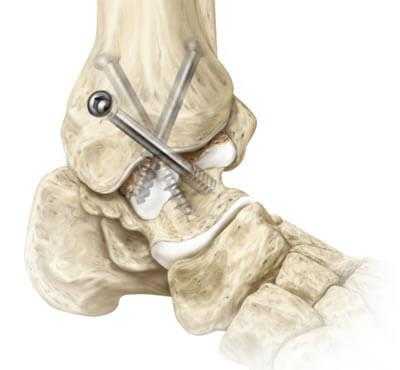

Артродез голеностопного сустава.

Ранее золотым стандартом хирургического лечения был артродез — операция, направленная на полное обездвиживание голеностопа. С одной стороны, она помогала избавиться от хронических болей. С другой — изменяла биомеханику стопы и всей конечности, из-за чего нарушалась динамика ходьбы и нередко возникала хромота. Поэтому от артродеза стали отказываться, а вместо него начали выполнять эндопротезирование.

Артродез голеностопного сустава - оперативное вмешательство по искусственному сращению сочленяющихся суставных поверхностей голеностопа в физиологически выгодном для функционирования ноги положении. Основной целью хирургического лечения является придание опоропрочности проблемной зоне посредством полного блокирования ее подвижности (создания анкилоза). Обездвиживание достигается за счет жесткого соединения примыкающих концов костей сустава между собой специальными фиксаторами из металла (спицами, винтами, штифтами и пр.). Это позволяет прочно срастись суставным поверхностям друг с другом под нужным углом, то есть, привести сочленение в полное неподвижное состояние, что поможет пациенту избавиться от сильной боли и нестабильности стопы.

- Дальше стопа выводится из порочного положения. Большеберцовый элемент и таранный компонент плотно сопоставляют друг с другом в удобной с точки зрения физиологии позиции. Достигнутая позиция скрепляется металлической конструкцией необходимого типа.

- Используемые операционные ходы на завершающем этапе закрывают при помощи послойного ушивания мягких тканей с оставлением дренажа.